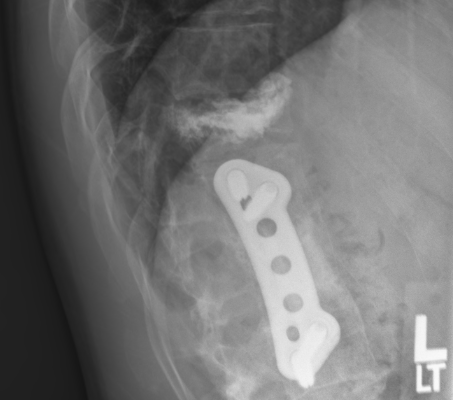

It’s been about a month since the doctors were able to perform a pretty miraculous procedure on my back. The accident burst my T11 vertebrae and since I already have a fusion and plates from T12-L2 the initial diagnosis was that to keep the spine supported they were going to have to fuse from T9 or T10 all the way down to L3 or L4 with the addition of rods/plates going from top to bottom of those locations. I told Dr. Sipos that I would prefer not to have such an invasive surgery and if he had any other options, initially he said that there was to much damage and that this was going to be the most feasible option, so I asked him to take a day or so and see if he could come up with any other options. He came to me the next day and said he had one other option of (for lack of better terminology) cementing the T11 vertebrae, removing all the extra bone fragments, and grinding down the portions that were pressuring the spine. It was not certain that it would work because of the amount of current injury and past injury, so he asked if I would like to take that option but if when he was performing the surgery he was not able to complete that option he had my permission to go with the full fusion from top to bottom as explained above. Of course I agreed and hoped for the best.

Needless to say his amazing talent worked out and he was able to perform the rebuilding of that vertebrae without having to insert and extra metal or fusions. Here are some pictures of what he was able to do and my current back.